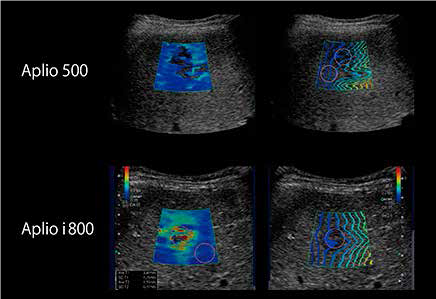

У нашому інституті ми використовуємо систему Aplio 500 Platinum, для досліджень SWE з 2014 року. Ми порівняли серії Aplio 500 та Aplio i-series, щоб побачити відмінності систем. Коефіцієнт кореляції між системами становить 0,96, демонструючи чудову послідовність.

У пацієнтів з метастазами в печінці часто відображаються вищі значення швидкості зсувної хвилі. Швидкість зсувної хвилі у 50-річної жінки з метастазами в печінці (рис. 8) розраховували за допомогою Aplio 500 та Aplio i800. На Aplio i800, на зображенні у B-режимі чітко зображено паттерн «бичаче око» на ураженні. Карта швидкості чітко продемонструвала жорсткість внутрішньої частини ураження, а карта поширення показала, що розповсюдження були більш паралельними, що дозволило краще інтерпретувати отримання SWE. Тонкий промінь дозволяє отримати менше артефактів від таких структур, як судини.

Рисунок 8. Порівняння Aplio 500 і Aplio i800 у випадку 50-річної жінки з метастазами в печінці